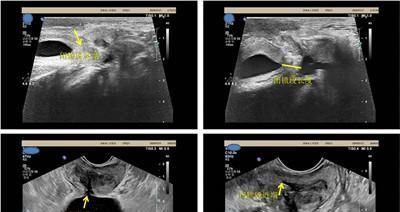

【与尿道造影相比,尿道超声影像学检查可动态观察尿道充盈及排空情况】

完善相关检查后,曾铭强博士联合超声科为患者进行尿道超声影像学检查。

患者在做尿道修复重建手术前,采取经会阴联合经直肠途径尿道超声检测,可以动态观察尿道闭锁的长度、瘢痕的程度。

以及前后尿道与周围组织的关系,能较好地评估手术的难度,了解尿道损伤有无并发症,这一技术的开展将造福众多尿道狭窄、闭锁患者。